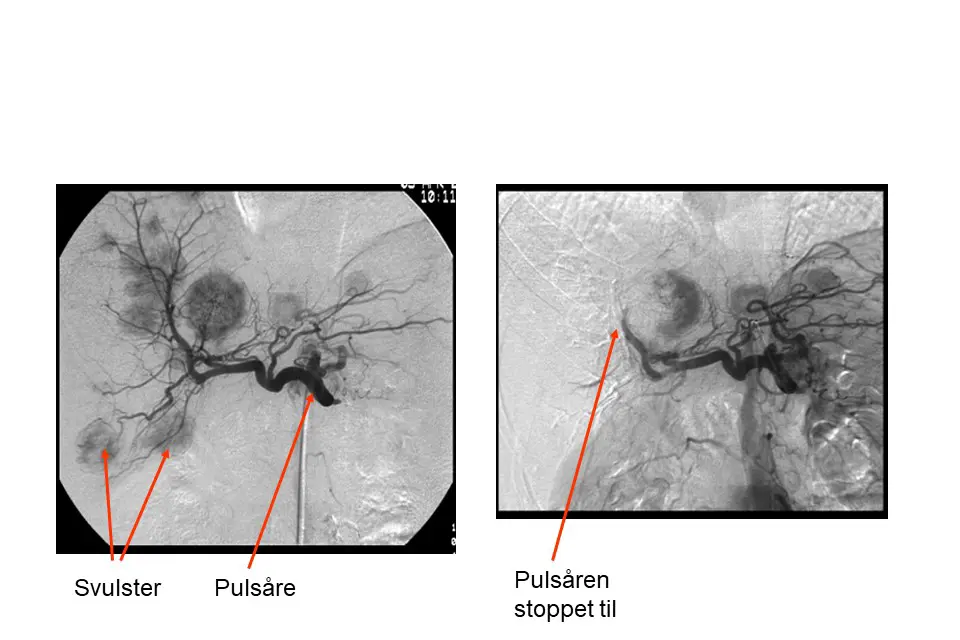

Arteriell leverembolisering

De normale levercellene får blod dels fra pulsåren (arteria hepatica) inn til leveren, dels fra portåren (vena porta) som bringer blod fra organene i magen til leveren. Kreftcellene får blod kun fra pulsåren.

Ved å stoppe til pulsårene til svulstene med små partikler kan man hindre blodtilførselen til svulstvevet og hele eller deler av svulsten vil dø. De normale cellene i området overlever fordi de også får blod fra portåren. Vanligvis stopper man til pulsårene til halve leveren av gangen. Behandlingen utføres ved at en røntgenlege fører inn et kateter til pulsåren til leveren via et innstikk i pulsåren i lysken. Gjennom dette kateteret sprøytes partiklene inn.

Embolisering av spredningssvulster til leveren: